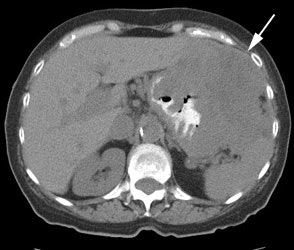

Gastrointestinal stromal tumor: The patient below had a large gastric GIST tumor (white arrow). FDG PET imaging demonstrated markedly increased, heterogeneous tracer uptake by the mass (black arrows). There was no evidence of metastatic disease. |